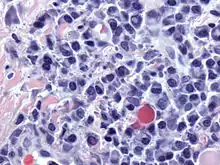

Bone marrow aspirate showing the histologic correlate of multiple myeloma under the microscope, H&E stain

Plasmacytoma, H&E stain

Atypical plasma cell infiltrate with both Russell (cytoplasmic) and Dutcher (nuclear) bodies (H&E, 50x)

Histopathology

A bone marrow biopsy is usually performed to estimate the percentage of bone marrow occupied by plasma cells. This percentage is used in the diagnostic criteria for myeloma. Immunohistochemistry (staining particular cell types using antibodies against surface proteins) can detect plasma cells that express immunoglobulin in the cytoplasm and occasionally on the cell surface; myeloma cells are often CD56, CD38, CD138, and CD319 positive and CD19, CD20, and CD45 negative.[20] Flow cytometry is often used to establish the clonal nature of the plasma cells, which will generally express only kappa or lambda light chain. Cytogenetics may also be performed in myeloma for prognostic purposes, including a myeloma-specific fluorescent in situ hybridization and virtual karyotype.

The plasma cells seen in multiple myeloma have several possible morphologies. First, they could have the appearance of a normal plasma cell, a large cell two or three times the size of a peripheral lymphocyte. Because they are actively producing antibodies, the Golgi apparatus typically produces a light-colored area adjacent to the nucleus, called a perinuclear halo. The single nucleus (with inside a single nucleolus with vesicular nuclear chromatin) is eccentric, displaced by an abundant cytoplasm. Other common morphologies seen, but which are not usual in normal plasma cells, include:

- Bizarre cells, which are multinucleated

- Mott cells, containing multiple clustered cytoplasmic droplets or other inclusions (sometimes confused with Auer rods, commonly seen in myeloid blasts)

- Flame cells, having a fiery red cytoplasm[65][66]